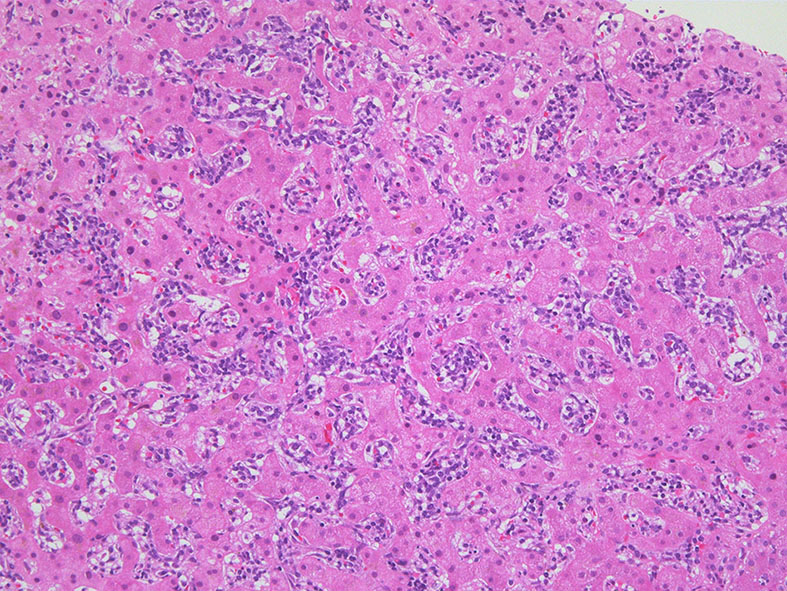

肝臓  サムネイルのクリックで大きな画像が見られます.

肝針生検組織; 類洞に細胞浸潤が認められ, 非浸潤部との境界がぼんやりと認められる. 類洞と異なり, グリソン鞘は腫瘍細胞の浸潤が乏しいか, ほとんど認められない.

類洞内に浸潤増殖するリンパ腫細胞: 類円形・長円, 瓜状の核をもつ,細胞質の乏しい細胞(サムネイル画像のクリックで大きな画像が見られます)